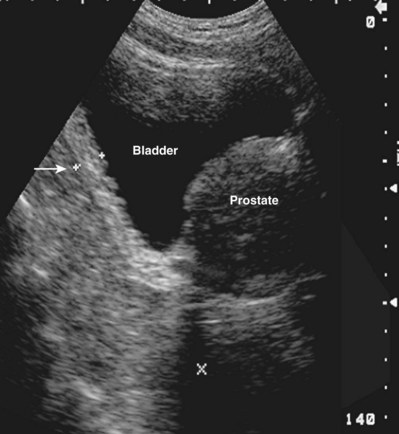

When urologists perform and interpret ultrasound studies, it is important that appropriate nomenclature be used to describe the objects imaged (Fig. 4–29). By convention, the liver is used as a benchmark for echogenicity. If a structure is hypoechoic, it means it is darker than the surrounding tissues. If it is hyperechoic, it means it is brighter than the surrounding tissues. Isoechoic means it is similar to the surrounding tissues. Structures that do not generate echoes are called anechoic. A simple cyst is an example of a structure with an anechoic interior. In general, a high water content causes tissue to appear hypoechoic. In general, a high fat content causes tissue to appear hyperechoic.

By convention, structures imaged by ultrasonography should be oriented so that the superior aspect of the structure is to the left as the image is viewed and the inferior aspect of the structure to the right. With paired structures it is critically important to document right or left. It is useful to use equipment-generated icons to illustrate patient position and the orientation of insonation (Fig. 4–30).